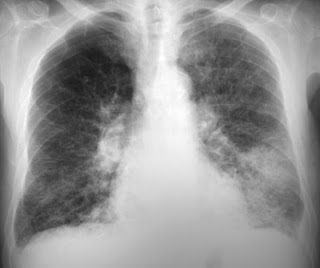

- Enfermedades pulmonares.

- Insuficiencia respiratoria aguda.

- Tuberculosis (TB).

- Neumonías bacterianas y virales.

- Ventilación mecánica.